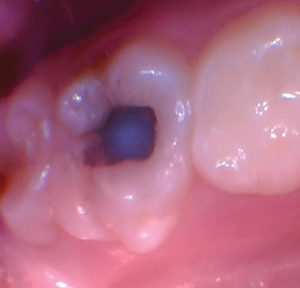

Figura 3. Con una forma de

conveniencia óptima lograda, las paredes periféricas y DEJ fueron excavadas a

fondo. La dentina afectada permanecía en el piso pulpar para evitar una

exposición pulpar. |

Figura 4. Se usó un microcepillo para aplicar fluoruro de diamina de plata a la dentina afectada. |

Figura 5. Ionoseal se colocó

en el piso pulpar y se curó, lo que aceleró la exposición del precipitado de

iones de plata (como lo demuestran los depósitos negros). |